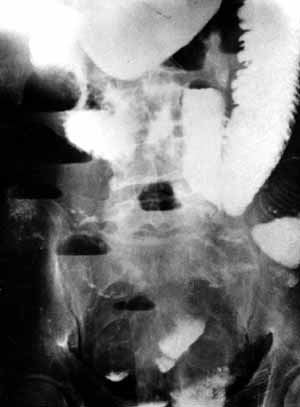

Рис. 4. Обзорная рентгенограмма брюшной полости того же больного после перорального контрастирования.

Новости лучевой диагностики 2002 1-2: 32-34